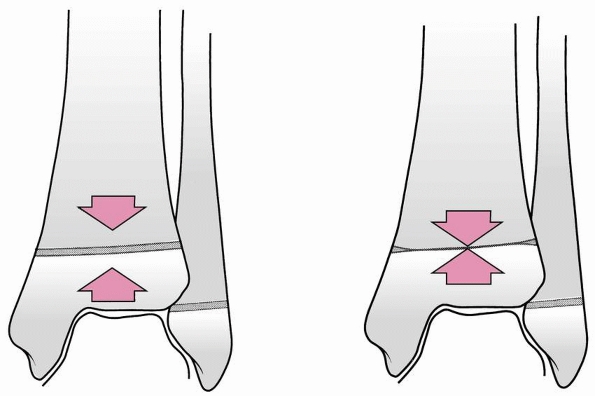

![]() |

FIGURE 26-33 A. Severely displaced pronation-eversion-external rotation injury. B.

Closed reduction was unsuccessful, and a valgus tilt of the ankle mortise was noted. At surgery, soft tissue was interposed laterally (arrows). C. Reduction completed and stabilized with two cancellous screws placed above the physis. |